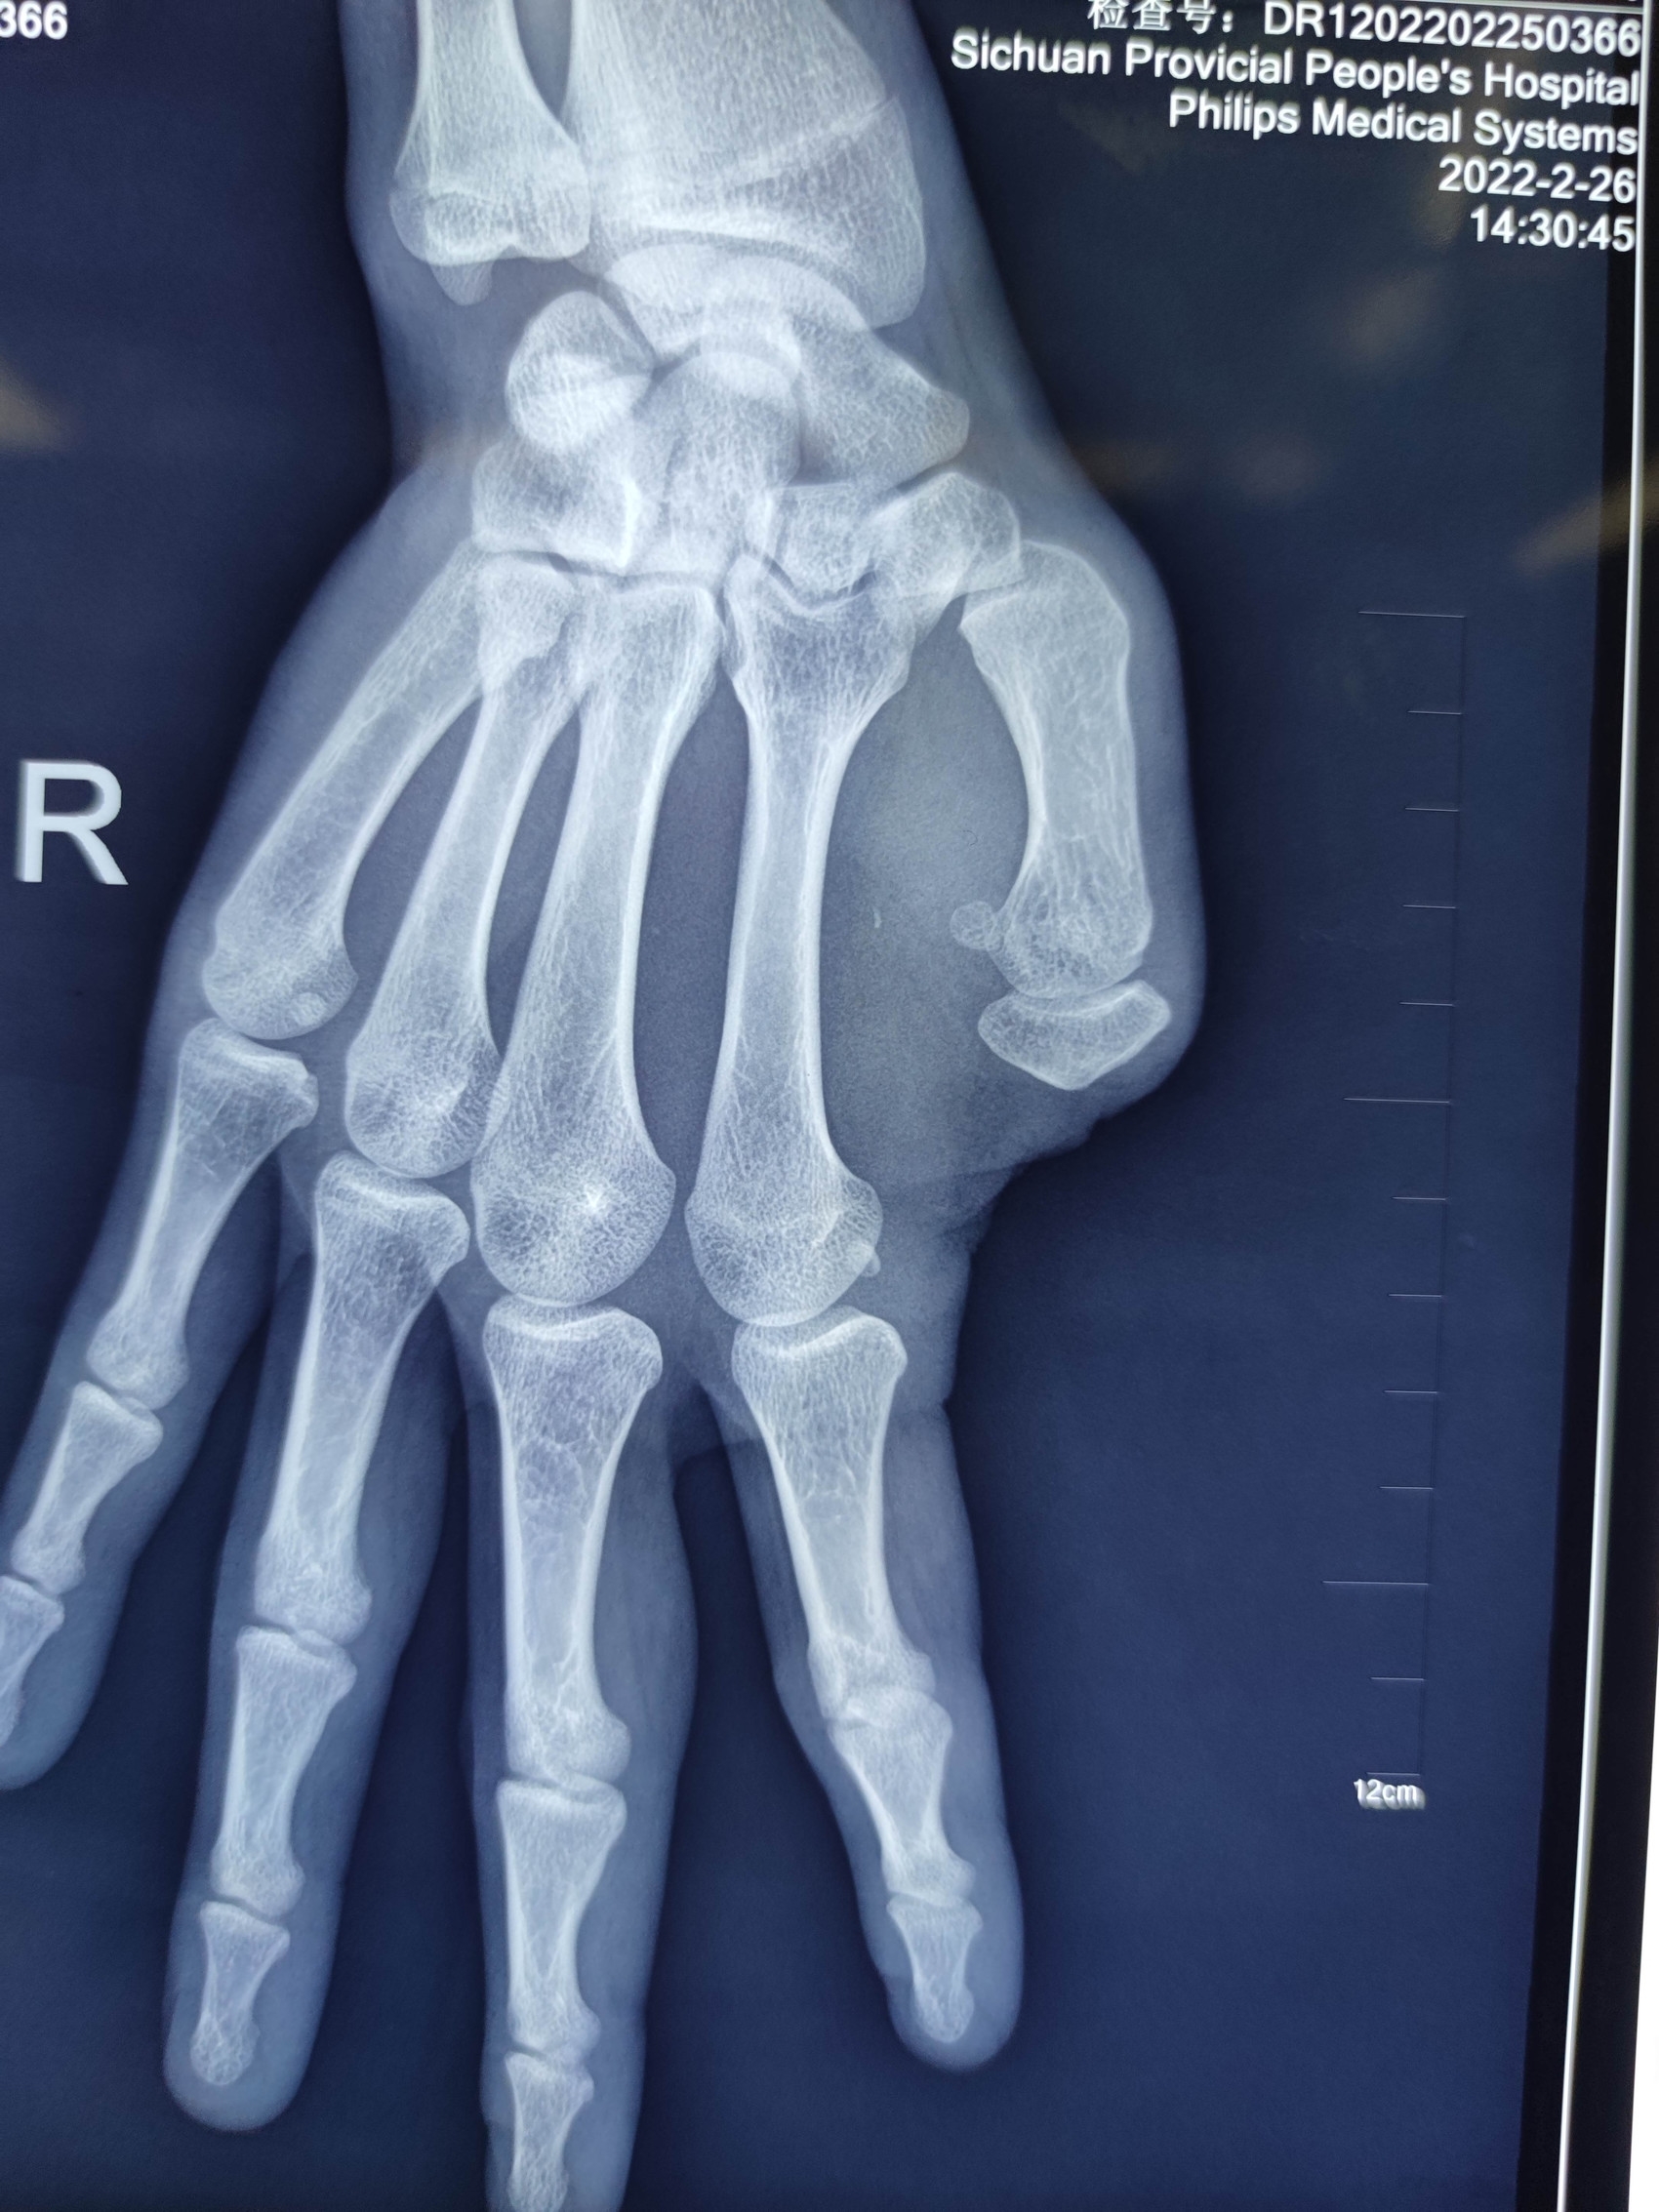

22岁小伙小杨,右拇指因电锯伤缺失10多年。因为右手拇指缺失,小伙一直苦恼不能写字,迫切希望能够用右手写字。走访多家医院后他最终来到四川省人民医院骨科就诊。术前的手照片以及影像资料显示右拇指缺失。